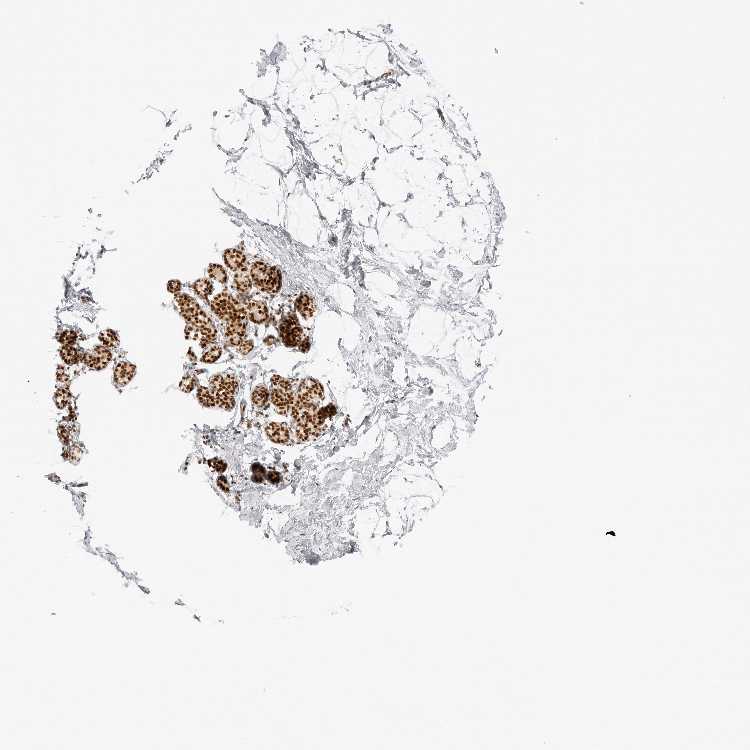

BREAST - Antibody stainingi

Antibody staining in the annotated cell types in the current human tissue is reported as not detected, low, medium, or high, based on conventional immunohistochemistry profiling in selected tissues. This score is based on the combination of the staining intensity and fraction of stained cells.

Each image is clickable and will lead to virtual microscopy that enables deeper exploration of all samples and also displays staining intensity scores, fraction scores and subcellular localization as well as patient and tissue information for each sample.

Antibody HPA027573Antibody HPA027574

Adipocytes MediumMedium

Glandular cells HighHigh

Myoepithelial cells MediumMedium